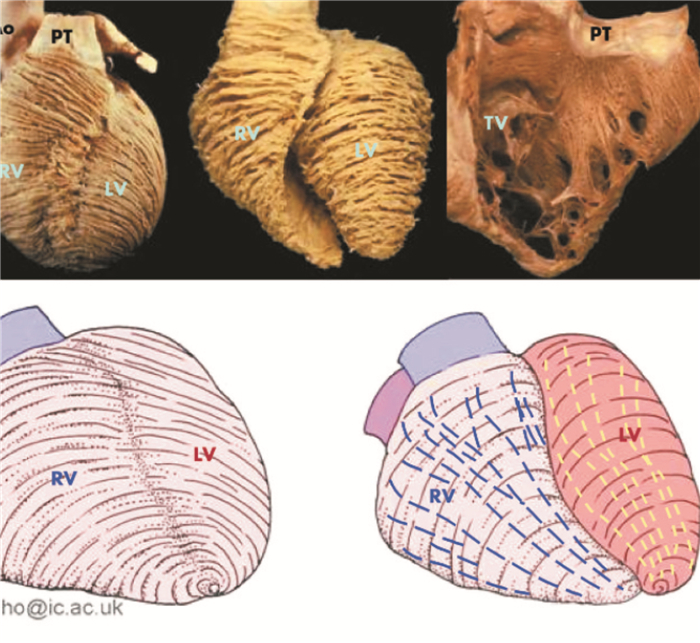

相对于左心室而言,右心室心腔形状较为复杂,并由三部分组成:带有三尖瓣的充盈腔室、具有游离壁的心尖部腔室和紧邻肺动脉瓣的右心室流出道。上述三个部分承担了右心室向肺动脉输送血液的重要任务[7]。右心室壁主要由浅和深两层心肌构成,浅层心肌基本上是平行于房室沟呈环形排列,倾斜并旋向心尖且与左心室表浅心肌延续;深层心肌从房室沟向心尖呈整齐的纵向排列,这种结构也决定了右心室心肌收缩的特点,即右心室收缩是一个相继的过程,开始于右心室流入部和心尖部肌小梁,终止于右心室漏斗部。右心室心肌的收缩过程可以通过以下机制来完成:右心室游离壁向内运动;纵向肌纤维运动使右心室长轴缩短,牵引三尖瓣环向心尖移位;左右心室心肌延续处心肌继发于左心室的收缩[8]。在这3个机制中,右心室收缩动力主要来自于纵向肌的收缩运动。由于左心室压力较右心室高,因而室间隔偏向右心室,在横断面上表现为新月形。三尖瓣的隔叶、前叶、后叶分别位于室间隔部、右心室游离壁前半部、后半部。右心室心腔主要由流入道、流出道两部分组成,流入道起自三尖瓣入口处,内壁较光滑,有粗细不等且较多的肌小梁附着在内壁的表面;流出道位于室上嵴的上方,上界为肺动脉瓣出口处,其内壁光滑,肌小梁较少。复杂的几何形状和心腔结构给人们对右心室的深入研究带来了极大的困难。所以,无论如何进行分段或采取微积分方法都难以精确计算其面积、容积如图 1,图 2所示。

A为前后位,显示右心室及右心室流出道、左心室及左心室流出道;B为右前位,显示明显的右心室的三角形状;C为俯视图,右心室呈新月形包绕着左心室;D心膈面明确显示冠状静脉窦;E明确显示四腔、三尖瓣及二尖瓣,虚线显示的冠状静脉窦横穿左房。 Ao, 主动脉;CS, 冠状窦;ICV, 下腔静脉;LA, 左房;LV, 左心室;PT, 肺动脉干;RA, 右心房RV, 右心室 图 1 心脏的腔室可以从上面的示意图中获得,蓝色为右心,红色为左心 |